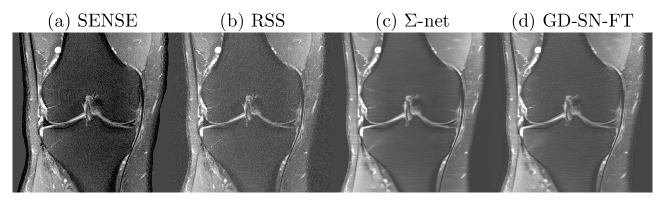

We present quantitative scores on the fastMRI validation set in Tab. 1 and qualitative results on a PDFS case for R=8𝑅8R\!\!=\!\!8 in Fig. 1. The ensembled ΣΣ\Sigma-net achieves the best SSIM scores. While the scores of SN-FT are low, it appears most textured and sharp compared to the ensembled ΣΣ\Sigma-net result.

Refer to caption

Figure 1: PDFS@1.5T (a) Fully-sampled sensitivity-weighted reference used for SN training (b) RSS target for quantitative challenge evaluation; (c) ensembled ΣΣ\Sigma-net (d) semi-supervised FT, for R=8𝑅8R\!\!=\!\!8.